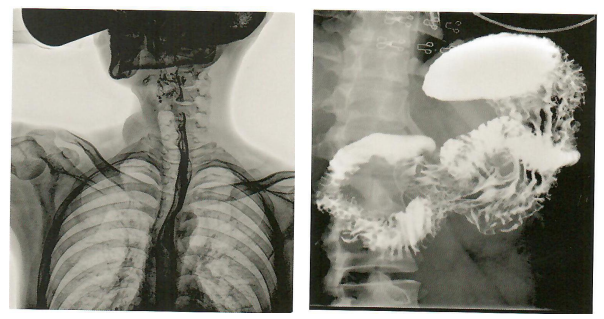

北斗系列数字透视摄影系统,毫秒抓拍,满足多种临床诊断需求,低剂量高转换率,瞬间曝光绿色安全,采用先进脉冲透视技术,结合高标准的硬件配置,使超低剂量与高清图像完美融合,全新的自动剂量控制系统,以更小的辐射剂量获取更清晰的图像信息,减少射线对医患的辐射。

精准诊断,卓越超群的影像质量,毫秒抓拍,满足多种临床诊断需求。

食道造影 胃肠造影

全消化道造影 其它照影